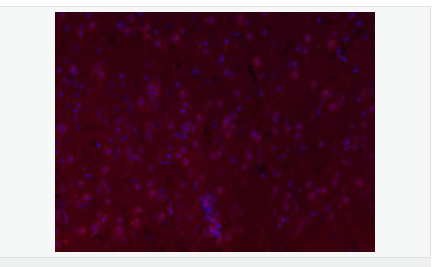

| 產品應用 | ELISA=1:5000-10000 IHC-P=1:100-500 IHC-F=1:100-500 IF=1:100-500 (石蠟切片需做抗原修復) not yet tested in other applications. optimal dilutions/concentrations should be determined by the end user. |

| 產品介紹 | This gene encodes a member of the fascin family of actin-binding proteins. Fascin proteins organize F-actin into parallel bundles, and are required for the formation of actin-based cellular protrusions. The encoded protein plays a critical role in cell migration, motility, adhesion and cellular interactions. Expression of this gene is known to be regulated by several microRNAs, and overexpression of this gene may play a role in the metastasis of multiple types of cancer by increasing cell motility. Expression of this gene is also a marker for Reed-Sternberg cells in Hodgkin's lymphoma. A pseudogene of this gene is located on the long arm of chromosome 15. [provided by RefSeq, Sep 2011] Function: Organizes filamentous actin into bundles with a minimum of 4.1:1 actin/fascin ratio. Plays a role in the organization of actin filament bundles and the formation of microspikes, membrane ruffles, and stress fibers. Important for the formation of a diverse set of cell protrusions, such as filopodia, and for cell motility and migration. Subunit: Associates with beta-catenin. Interacts with PLXNB3. Subcellular Location: Cytoplasm, cytoskeleton. Cell projection, filopodium. Cell projection, invadopodium. Cytoplasm, cytosol. Note=In glioma cells, partially colocalizes with F-actin stress fibers in the cytosol. Tissue Specificity: Ubiquitous. Post-translational modifications: Phosphorylation on Ser-39 inhibits the actin-binding ability of fascin. Similarity: Belongs to the fascin family. SWISS: Q16658 Gene ID: 6624 Database links: Entrez Gene: 6624 Human Entrez Gene: 14086 Mouse Omim: 602689 Human SwissProt: Q16658 Human SwissProt: Q61553 Mouse Unigene: 118400 Human Unigene: 289707 Mouse Unigene: 199526 Rat Important Note: This product as supplied is intended for research use only, not for use in human, therapeutic or diagnostic applications. FSCN1為細胞骨架肌動蛋白的一種,該蛋白有蛋白結合,橋連、肌動蛋白絲結合的功能。 主要參與細胞增殖、肌動蛋白細胞骨架組織和生物發生、肌動蛋白絲束形成。Fascin也是一種actin結合蛋白,它的功能是把F-actin聚集捆綁成束,與細胞的運動相關。病理情況下,各種惡性腫瘤細胞經常高表達Fascin。 |